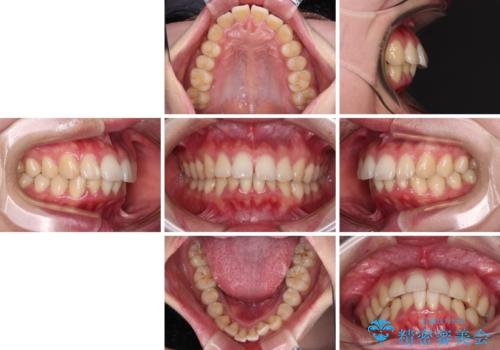

飛び出した上顎前歯 抜歯矯正でスッキリとした横顔に

- 下唇に跡がつくほどに飛び出した上顎前歯を気にして来院された患者様です。

来院された時から4本の抜歯が必要であることを理解されていらしており、通法通り上下左右の第一小臼歯4本を抜歯し、ワイヤー装置にて矯正治療を行うこととしました。

順調に治療が進み、2年弱で想定していたとおりの仕上がりにて治療を終えることができました。